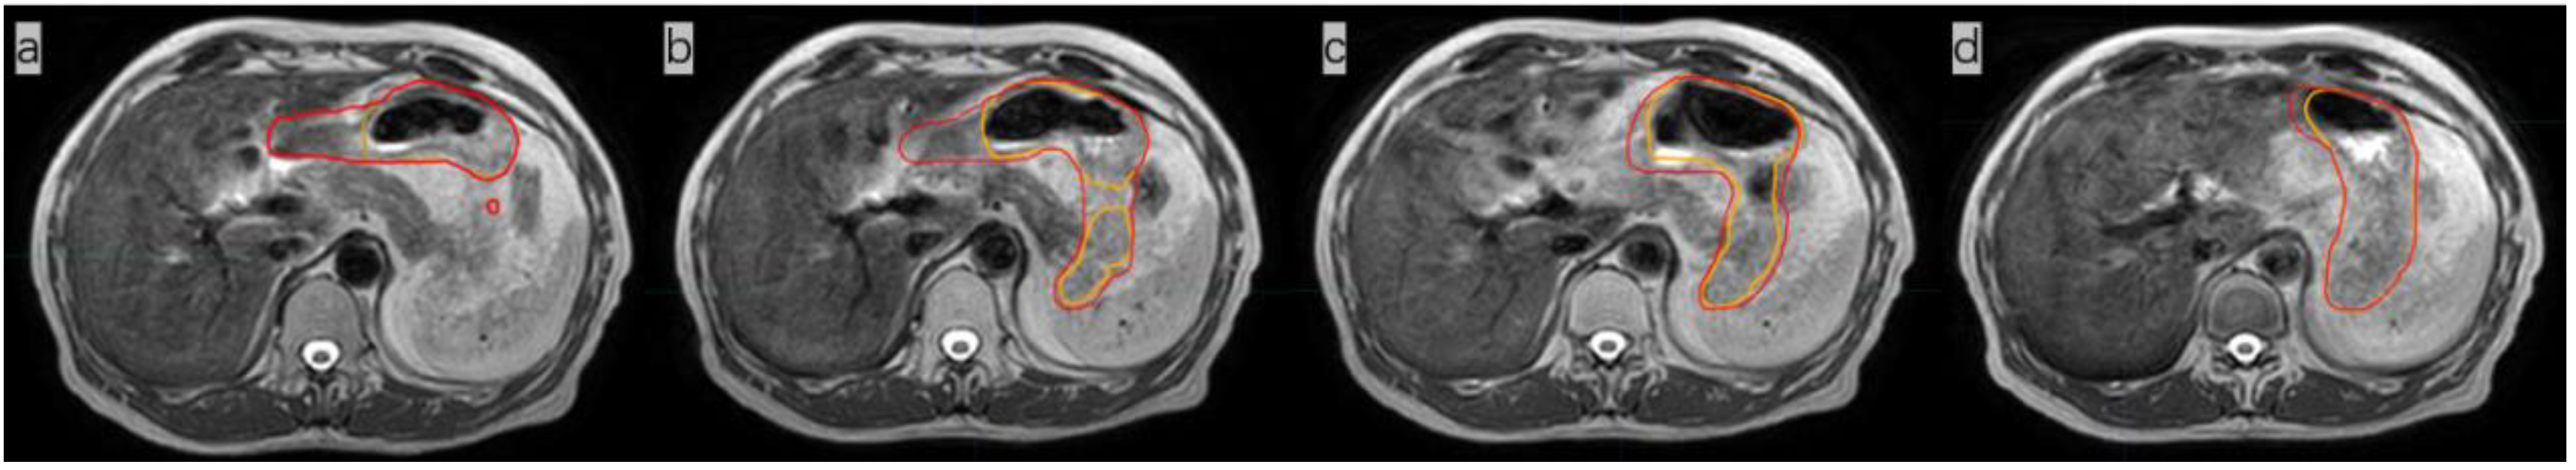

Figure 1.

(a). Magnetic resonance image (MRI) of a patient (not the patient treated in this study) not treated with anisodamine; notice that the outline of the stomach is blurred (yellow arrow); (b) MR image of the patient treated with anisodamine; notice that the outline of the stomach is clearer (green arrow; the red line indicates the contours of the whole stomach).